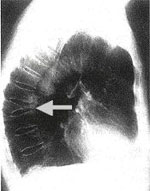

Röntgenbild der Brustwirbelsäule. Der Pfeil markiert einen eingebrochenen Wirbel (rechts)